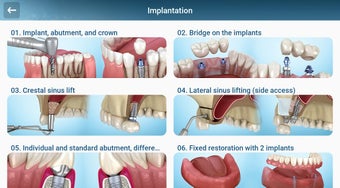

إذا كنت متخصصًا في طب الأسنان أو مريضًا، فقد تساعدك هذه الأداة في تعلم علاجات الأسنان.

يستند التطبيق على مبدأ عرض الشرائح. يحتوي كل موضوع على 3-9 صور. يمكن عرض صور أي موضوع في أي وقت.